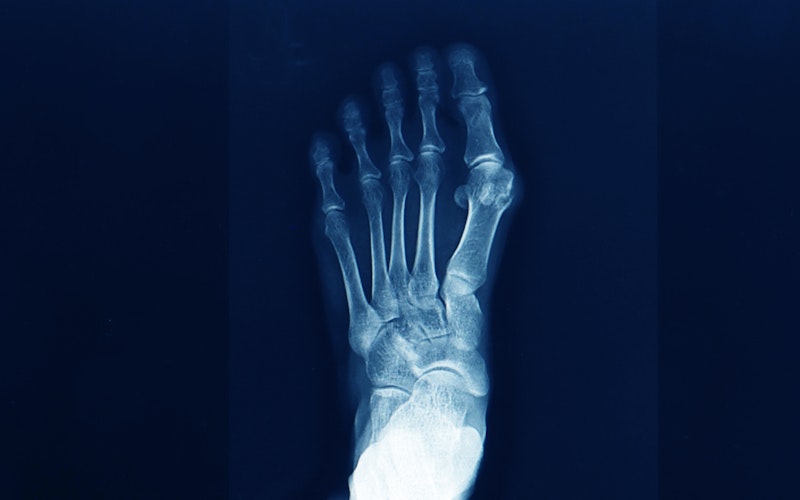

If you're dealing with foot pain, bunions are easy to spot. Unlike other foot conditions such as corns, calluses, or ingrown toenails, bunions are predominantly found along your big toe.

A Closer Look at Bunions If this seems familiar, visit our Romeo, MI, doctor.